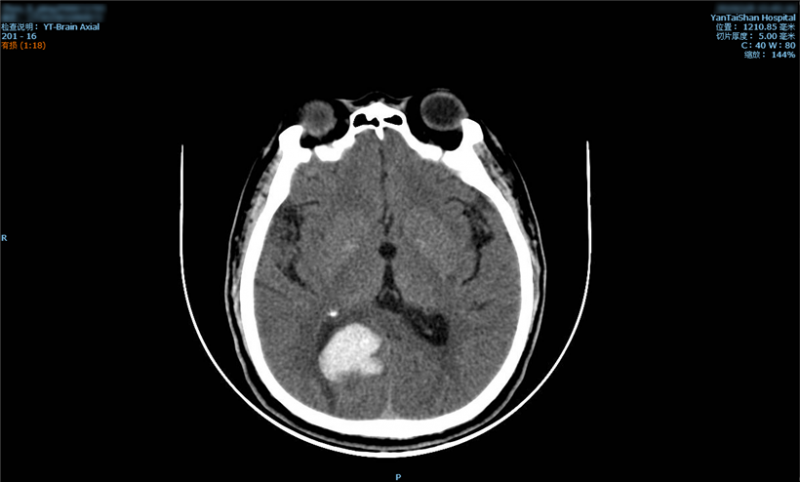

烟台山医院神经外科主任刘建辉在为患者检查时判断,患者虽然手脚灵活、没有偏瘫、吐词清楚、问答正确、没有面瘫,但仍有可能是脑出血,他建议周老汉做一个颅脑CT检查。周老汉在家人的陪同下接受了CT检查,检查结果显示:患者枕叶脑出血。刘建辉主任分析说,“枕叶是管理人视觉的大脑区域,这一部位出血,影响到了患者的视觉,所以他才有了‘鬼打墙’的幻视。”

颅脑CT显示:患者枕叶脑出血